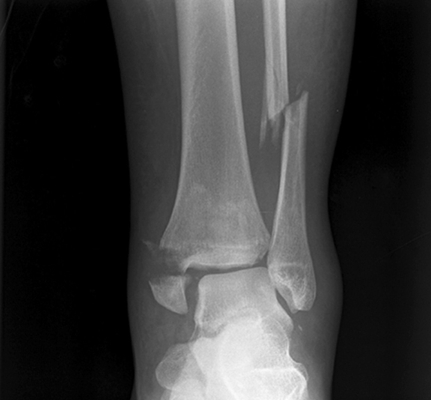

骨折圖片